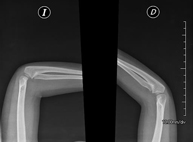

- RX Extremidades

Técnica mediante la cual, utilizando rayos X, se obtienen imágenes del interior de las extremidades para su estudio, especialmente de los huesos. Indicaciones: traumatismo, infecciones articulares. - RX Artrografía

Técnica mediante la cual, utilizando rayos X, se obtienen imágenes de la totalidad de ambas extremidades inferiores para su estudio, valorando especialmente la presencia de dismetrías entre ambas. - RX Extremidades

Técnica mediante la cual, utilizando rayos X, se obtienen imágenes de ambas extremidades para su estudio. - RX Caderas